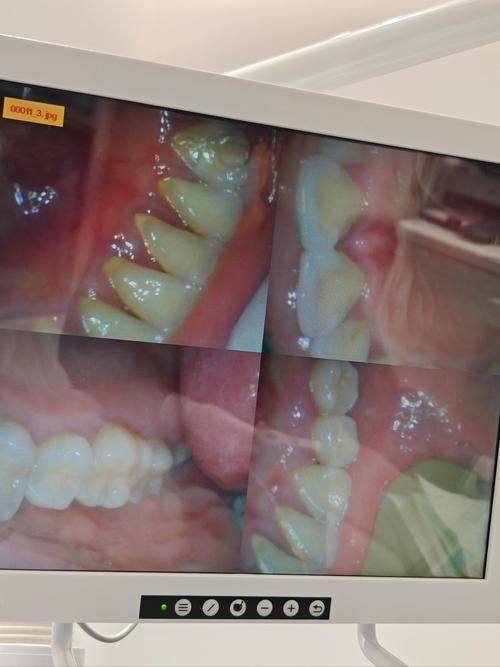

医院的技术实力直接关系到患者的治疗成效。贵阳利美康口腔(金阳分院)自1991年成立以来,累计服务超百万患者,现拥有10间诊室、22张牙椅、150 - 200人医护团队,覆盖种植、正畸、修复等全领域。自建齿科加工厂,从种植体到牙冠,实现生产 - 诊疗闭环,源头把控质量,缩短患者等待时间。在技术设备方面,引入DSD微笑设计、iTero口扫仪、三维CT等设备,实现种植与隐形矫正。部分支持“当天种牙当天用”的即刻负重种植技术,解决了缺牙患者即时饮食需求。院长及骨干医生均具备10年以上临床经验,如正畸陈娟、种植罗幼刚等,擅长复杂病例的治疗。